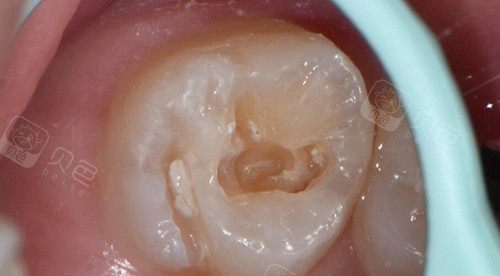

补牙步骤图

一、基础补牙:树脂材料主导市场,价格跨度大

树脂补牙是东莞比较主流的补牙方式,因其美观性、耐磨性和生物相容性,被广泛应用于前牙和后牙修复。根据材料品牌和牙齿缺损程度,价格分为以下三档: